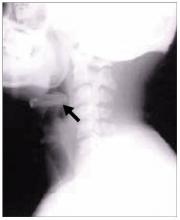

Figure 3. Left, fundus photo several weeks after an attack of nonarteritic anterior ischemic optic neuropathy demonstrating pallor of the superior half of the disc. Middle, an associated inferior altitudinal defect. Right, sectoral swelling of the disc with flame or splinter hemorrhages is commonly seen. This is not typical of demyelinating optic neuritis.

Nonarteritic anterior ischemic optic neuropathy is the most common form. Typically, there is acute onset of painless vision loss in one eye and an associated altitudinal field defect (Figure 3). For example, if the superior rim of the optic nerve acutely develops swelling and then becomes pale, a corresponding altitudinal cut would develop in the inferior visual field, respecting the horizontal meridian. Many patients first notice the vision loss upon waking up in the morning.13

Although patients with nonarteritic anterior ischemic optic neuropathy typically have vasculopathic risk factors such as hypertension, diabetes mellitus, peripheral vascular disease, or hypercholesterolemia, there is no proven causation between the two. The age of these patients ranges from 50 to 70, with an average age of 66.

The disc appears swollen and may have flame or splinter hemorrhages (Figure 3). The cup of the involved disc is typically small. The visual loss is believed to be the result of poor perfusion in the circulation of the posterior ciliary artery, which supplies the optic nerve head.1 If the other eye also has a small cup, it is considered to be at risk of future ischemic events. In one study,14 the opposite eye became involved within the next 5 years in 14.7% of all cases. The risk of recurrent disease in the same eye is low (6.4% in another study15).